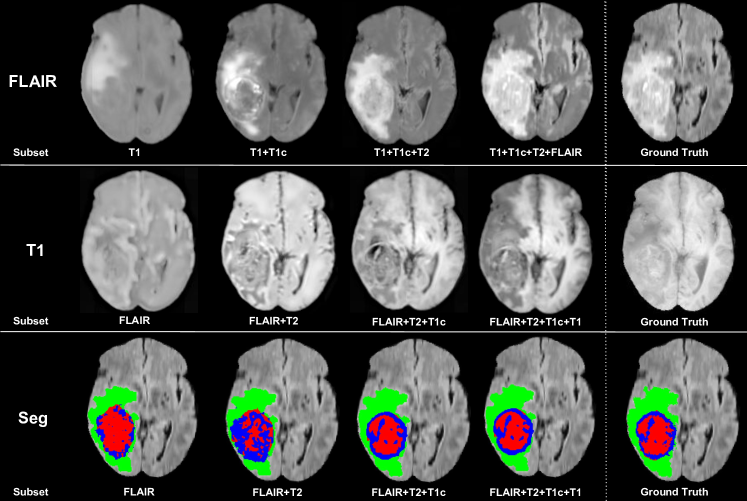

Unlike these three approaches, U-HVED (Ours) generates missing modalities. Since image completion is a means rather than an end, we only provided a qualitative evaluation (Fig. 3) of T1 and FLAIR reconstruction examples. We find the reconstruction to be good quality, given that VAEs classically suffer of blurriness. Interestingly, our model tries to reconstruct the tumour information even when the tumour information is missing or not clear, such as in T1 scans. Moreover, comparable reconstructions are performed using 3 modalities and 4 modalities. This suggests that our network can effectively learn a common representation of the imaging modalities.

4.0.3 Tumour segmentation.

In order to evaluate the robustness of our model, we present qualitative results in Fig. 3 and comparative results with other methods in Table 1 for all the possible input subsets. We used the Dice Similarity as metric. First, the U-Net architecture in U-HeMIS always achieves better performance than the original 2D fully-convolutionnal HeMIS. This highlights the efficiency of the 3D U-net architecture. Secondly, U-HVED (Ours) outperforms significantly U-HeMIS in most of the cases: 13 out of 15 cases for the complete tumour, 10 out of 15 cases for the core tumour; 11 out 15 cases for the enhancing tumour. This demonstrates that auto-encoding and modality completion improves the segmentation performance. Finally, U-HVED achieves similar performance to the 15 subset-specific models (Single). Again, this suggests that the imaging modalities are efficiently embedded in the latent space.